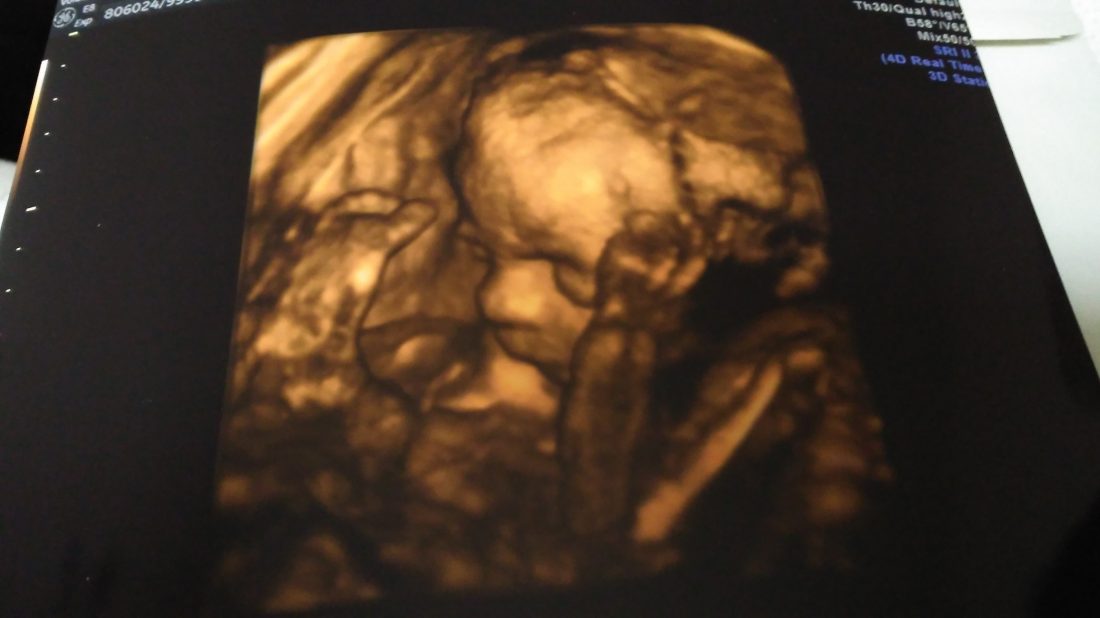

V pátek jsme byli objednáni na 4D ultrazvuk. Moc jsem se na něj těšila, až uvidíme našeho drobečka. A jak to tak bývá, čím víc se těším, tím je jasnější, že to asi nedopadne úplně dobře. A bylo to tak. Prcek se nám schovával, před obličejem měl ručičky, stále si hrál s nožičkama, které přitahoval též k obličeji a chytal si je ručičkama. Zkrátím to, ultrazvuk jsme jednou přerušili v domnění, že procházka po schodech pomůže a prcek se nám ukáže, ale chyba lávky. Výsledkem byly celé dvě fotografie, jedna, kde se na nás náš poklad pěkně mračí, a vypadá dost naštvaně (asi se mu ta návštěva nelíbila), a pak naštěstí i jedna normální, krásná fotečka. 🙂 Jediné pozitivum bylo, že jsme ušetřili pár stovek za video, ale upřímně, raději bych to video s naším prckem. 🙂 Nicméně na další 4D se již nechystáme, myslím, že nám náš poklad dal jasně najevo, co si o takovém nabourání soukromí myslí. 🙂

Ultrazvuk měl ale ještě jedno pozitivum. Ujistil mě totiž, že je prcek v pořádku. V posledních dnech mi totiž přišlo, že jeho pohyby necítím tak intenzivně a tak často jako cca ještě před týdnem. Nakonec jsme se s paní doktorkou shodly, že byl asi jen jinak natočený. Nyní ho totiž opět cítím dostatečně, někdy až dost. 🙂 Dělám si z muže srandu, že to bude malý fotbalista (on totiž fotbal nemá rád), podle něj to však bude spíš malý karatista. 🙂